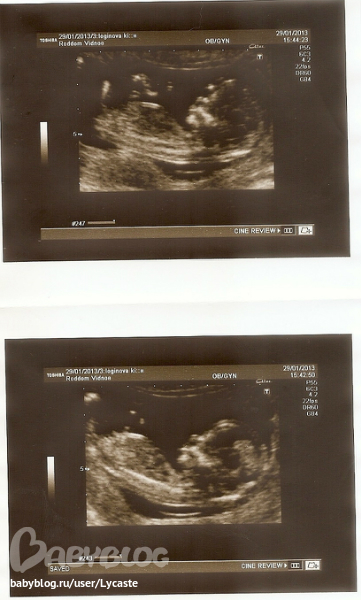

БПР 80.7мм 32.1 нед

ОГ 290 мм 30.5 нед

ОЖ 267.8мм 30.5 нед

ДБ 60.2 мм 30.6 нед

ПМП 1700+- 200 гр

плацента по передней стенке

тепень срелости 1

воды норм

пуповина 3 сосуда

Обвития нет

ЧСС 152 уд\мин

Подтвердили девочку))))

толщина рубца 2.4 мм